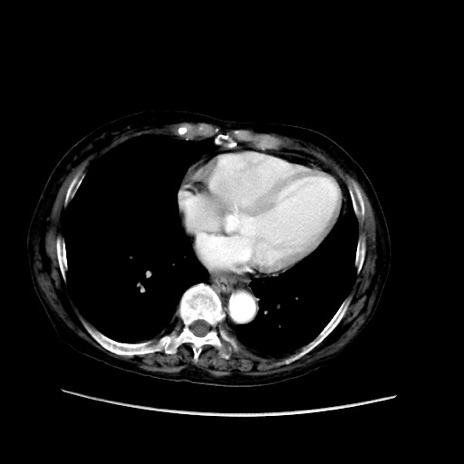

症例31(横断像)

【症例】80歳代 女性

【主訴】腹部膨満感

【現病歴】他院にて肝硬変にてフォロー中。1週間前から便秘、腹部膨満感、臍部腫瘤あり受診となる。

【既往歴】肝硬変

【身体所見】腹部膨隆あり、皮膚変化なし、疼痛なし。

【データ】WBC 4600、CRP 0.25